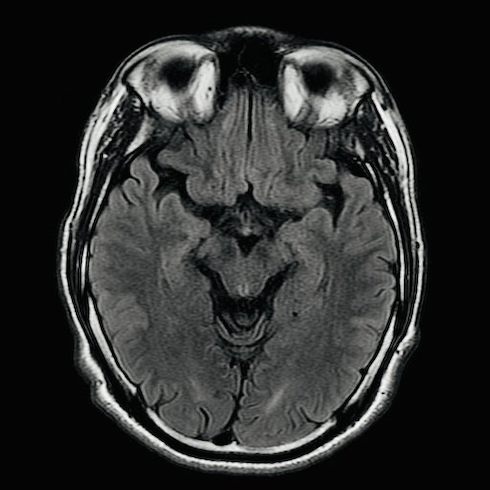

今回は、研究のために撮影した自身の脳のMRI画像が注目を集めました。投稿した2枚の写真では、横からの断面はごくごく普通の頭部に見えますが、上からの断面は邪悪な笑みを浮かべる口のように見える部分が存在しています。

真田さんは「『俺の頭ってこうなってるのか〜』って感心してたら、急に闇堕ちした熊のプーさん登場してやばかった」とコメントしました。確かに、口の少し上がクマの鼻、その両側が不気味な笑みを浮かべる目、上端の眼球部分がクマの耳と考えると、2023年公開のホラー映画「プー あくまのくまさん」に登場する“闇堕ちしたプーさん”にそっくりです。